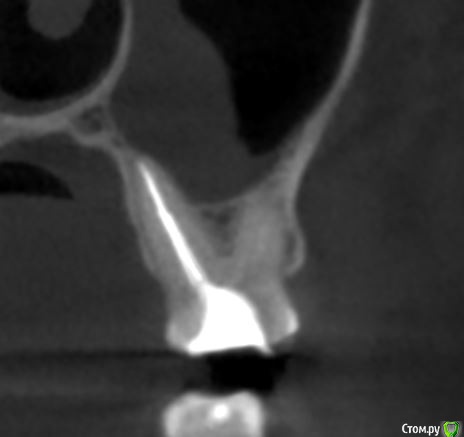

krokomot Опубликовано 19 февраля, 2020 Поделиться Опубликовано 19 февраля, 2020 в медиальном корне недопломбировка и наличие вероятно 4ого канала. Ссылка на комментарий

dmitrib81 Опубликовано 20 февраля, 2020 Автор Поделиться Опубликовано 20 февраля, 2020 Зуб делали много лет назад. Примерно неделю назад появились периодические боли, бывает целый день не болит, потом снова ноющая боль. С приёмом пищи никак не связано. На горячие и холод реакции нетПодскажите, может ещё прислать фоток из КТ Пикассо, а то я в этом ничего не понимаю, просто разных фото экрана прислал, без какого-либо понимания, на что смотреть.. Ссылка на комментарий